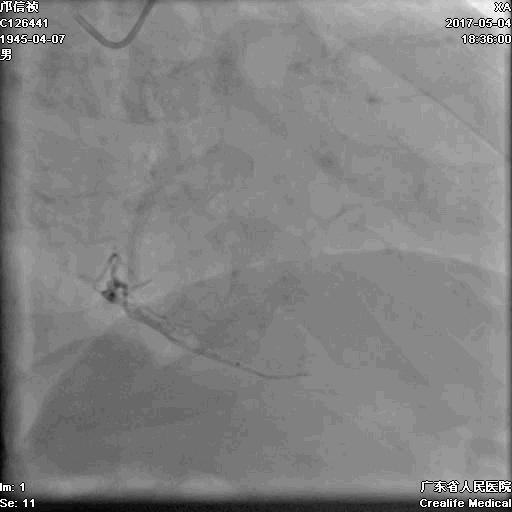

第二步:处理LCX

Fielder XT-A,Gaia First ---在微导管支撑下通过闭塞病变

LCX植入支架

2.0*10mm球囊

2.75*22mm药物支架